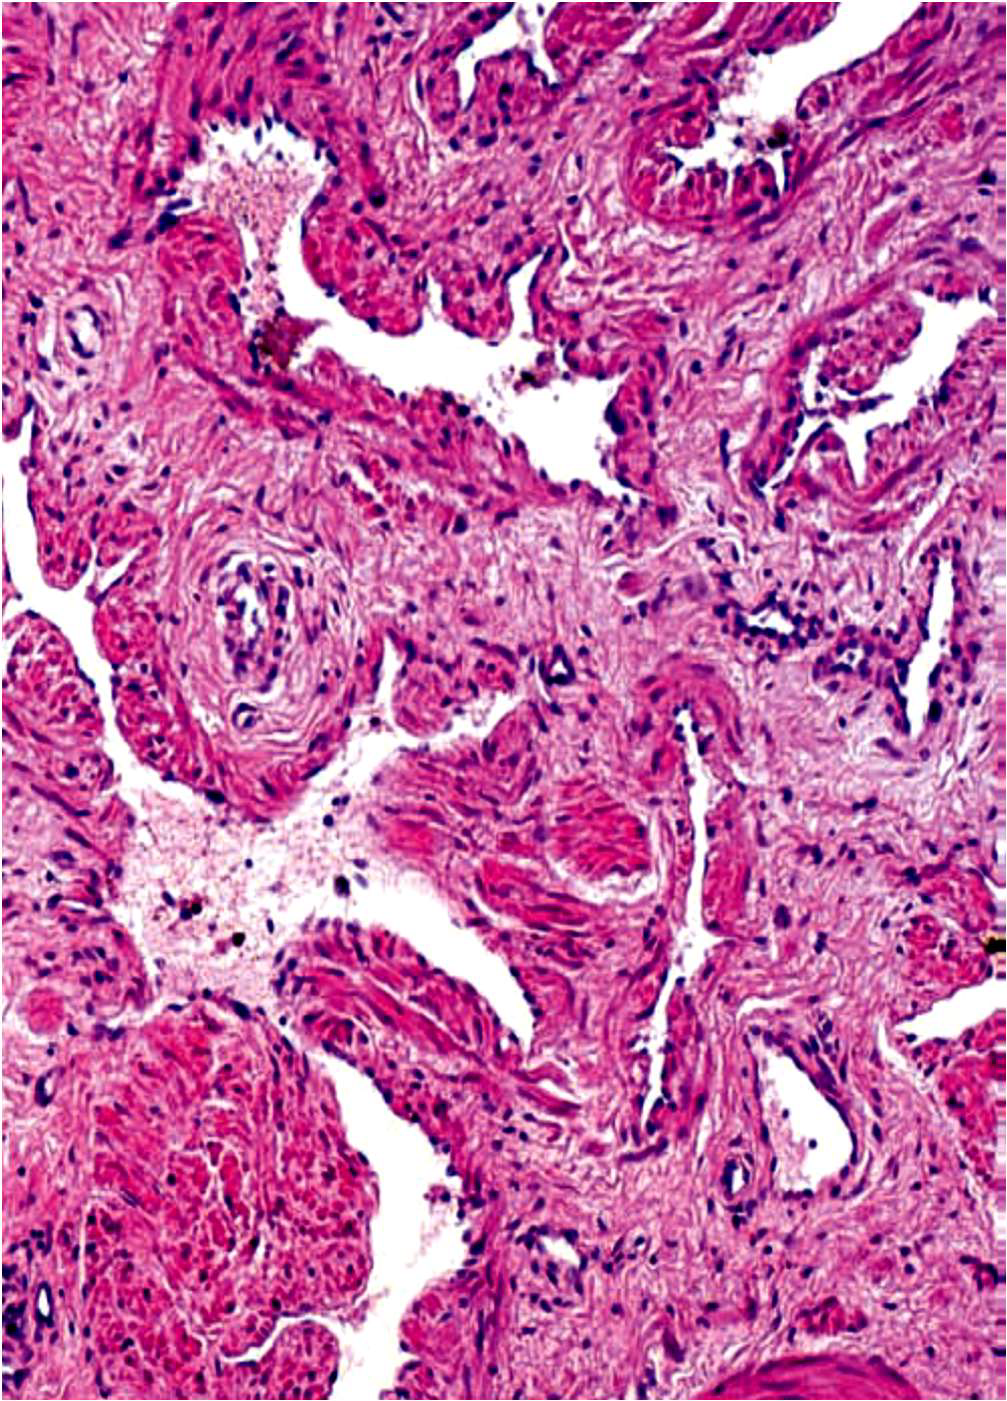

Prostate Gland

- Peripheral zone

- Transitional zone

- Prostatic concretions (CA)

- 年輪狀,填在線體裡面

- Tunica albuginea (Deep fascia)

- Trabecular

- Penile Urethra